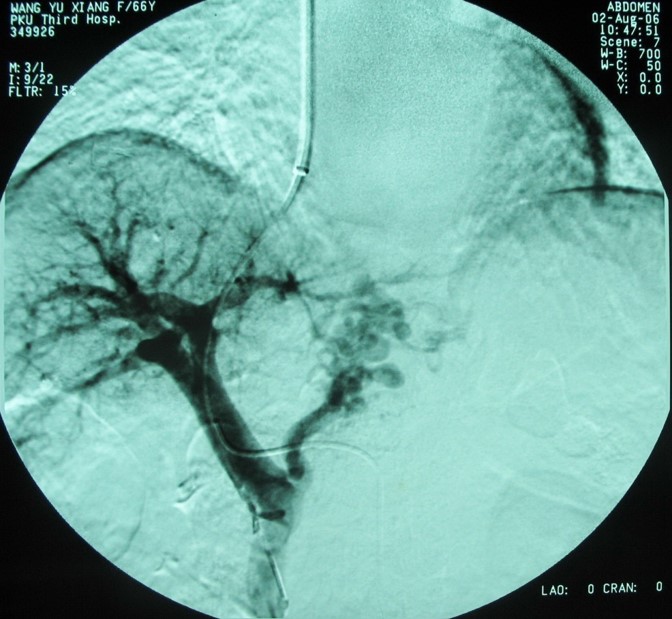

肝靜脈壓力梯度測(cè)定(HVPG)

對(duì)門靜脈高壓進(jìn)行精確量化評(píng)估和危險(xiǎn)度分層,指導(dǎo)不同危險(xiǎn)分層治療策略,本技術(shù)省內(nèi)領(lǐng)先。

肝靜脈壓力梯度測(cè)定